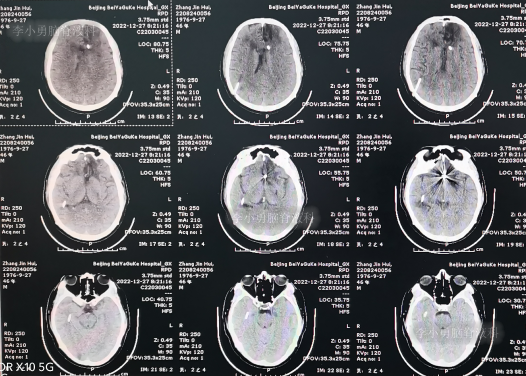

2022年9月27日(住院治疗34天),患者出现意识差,查头颅CT示颞角扩张(图-18)。

图-18:2022年9月27日头颅CT

当天进行了颞角和侧脑室腹壁外引流术(图-19)。

图-19:2022年9月27日术后头颅CT

2022年10月12日(住院治疗49天),脑脊液真菌彻底消灭,查头颅CT示颞角缩小(图-20)。

图-20:2022年10月12日头颅CT

脑脊液各项化验均正常后于2022年12月14日(住院治疗112天),进行了脑室腹腔分流术(图-23)。

图-23:2022年12月14日头颅CT

2022年12月27日(李小勇脑脊液科治疗125天)康复出院,出院时:神清气爽,心情愉悦,走路基本正常,言语交流正常(图-24);出院时头颅CT示未见异常(图-25)。

图-25:出院时头颅CT